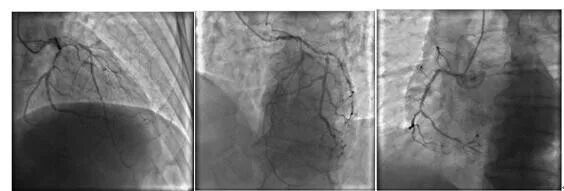

▲冠脉造影示:回旋支重度狭窄;前降支近端重度狭窄,全程弥漫性狭窄;右冠重度狭窄

▲成功剥除颈动脉内膜,术中颈动脉超声示颈动脉血管流通完好

最终决定由心血管外科联合神经外科进行“颈动脉内膜剥脱联合冠脉搭桥同期手术”。手术先由神经外科杨新宇主任进行颈动脉内膜剥脱手术,术中成功剥除颈动脉狭窄段内膜斑块,颈动脉彩超提示颈动脉血管流通完好;随后马上由心脏外科梁德刚主任成功完成冠状动脉旁路移植术(1支动脉桥,3支静脉桥)。

▲成功完成了冠状动脉旁路移植(1支动脉、3支静脉),术后李大爷伤口甲级愈合,意识清楚,恢复良好,活动正常